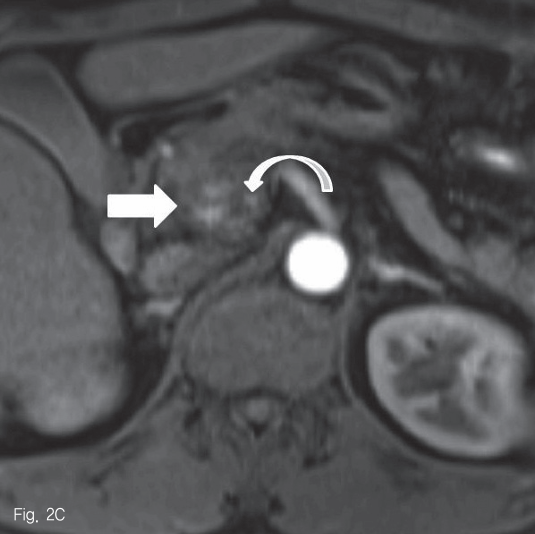

초음파 검사에서 췌장 두부에 약 2.5cm 크기의 종괴가 있었다 (Fig. 1). 췌장 자기공명영상에서 종괴는 T1-weighted image에서 다양한 신호강도를 보였고, T2-weighted image 에서는 저신호강도를 보여 다양한 단계의 출혈을 포함한 병변으로 생각하였다 (Fig. 2A-B). 조영 증강 자기공명영상 및 조영 증강 복부 전산화단층촬영에서 종괴의 내측으로 혈관과 비슷한 조영 증강을 보이는 1cm 크기의 병변이 보여 가성동맥류로 진단하였다 (Fig. 2C-D).

Fig 1

Abdominal sonogram reveals a 2.5cm-sized mass in pancreatic head (cross signs).